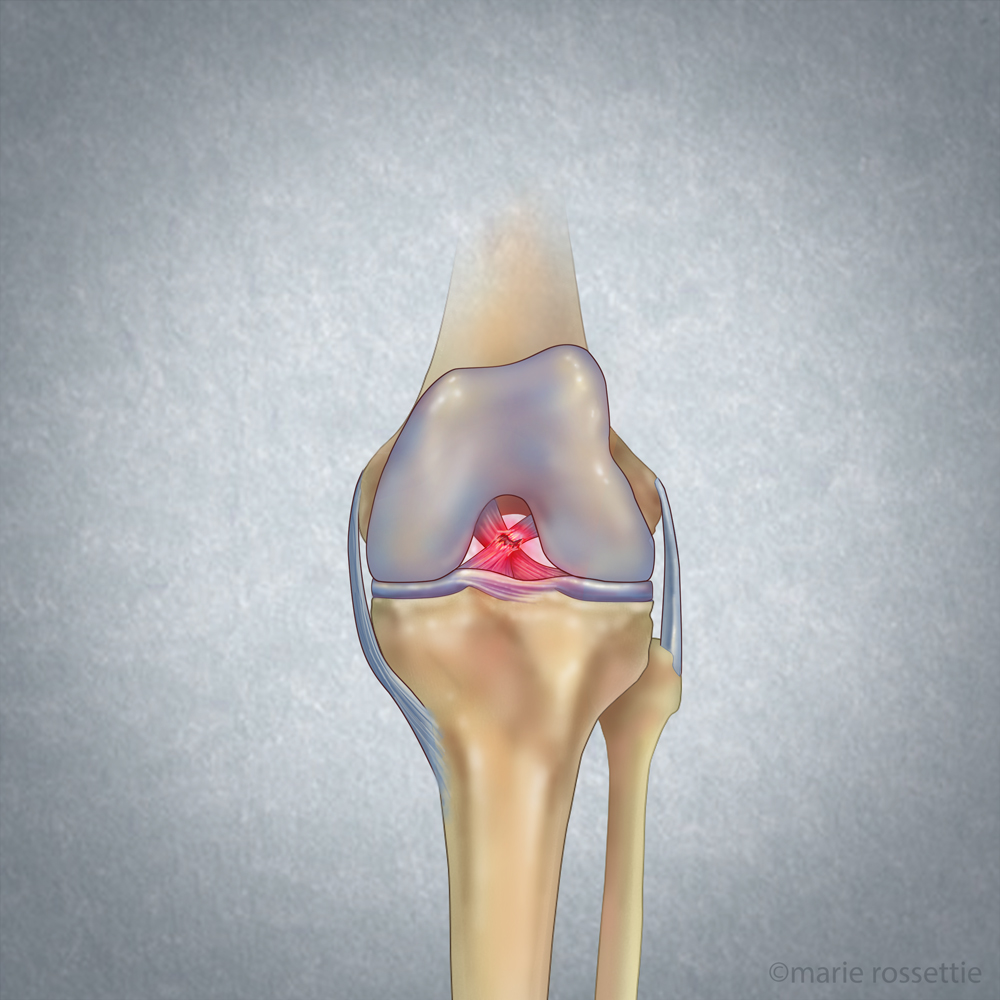

Shown above is a torn ACL